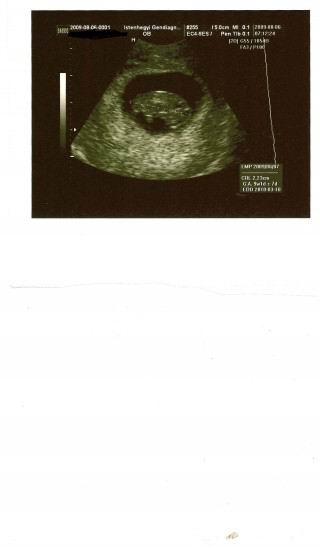

mai sztárfotónk

mai sztárfotónk2009.08.06 15:58